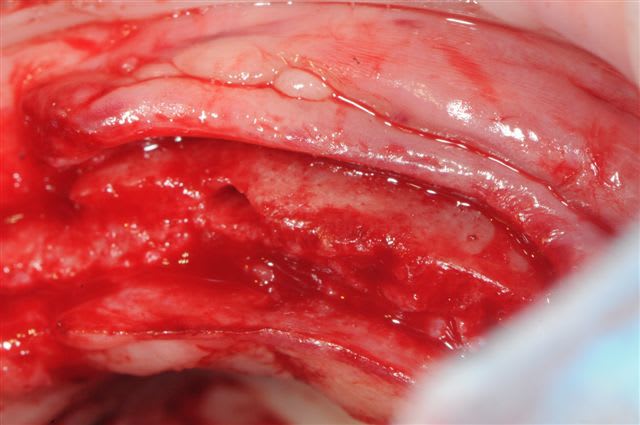

c'est en cours d’intégration, la zone n'est pas "creuse" mais en remaniement, c'est surtout l'os de la patiente, qui trop fin au départ a du mal à suivre.

Concernant la résorption du greffon, même constatations que Growler: aucune, les seuls zones qui ont fait reculer la date d'intervention, de 2 mois sont des zones de jonction avec l'os du patient qui avait du mal à fusionner car trop fin au départ (moins d'un mm)je pense.

Nous ne sommes pas sur la même longueur d’onde. Lorsque tu m’as demandé de travailler sur le projet, Biobank n’était pas en mesure de répondre à ta demande. J’ai réalisé une procédure confidentielle pour usiner un greffon de façon manuelle dans des conditions de livraison respectant les données acquise de la science. Comme pour le développement du guide chirurgical j’ai pris le maximum d’information pour connaitre les critères à respecter, un des critères (et cela peut répondre à l’interrogation de pluton) la partie corticale semble être plus longue à se résorber et permettre une meilleure formation osseuse, ce que l’on voie souvent dans ce type de reconstruction ce sont plusieurs greffons en domino ostéosynthésés et souvent en spongieux plus facile à conformer après ouverture du lambeau. Ce que j’ai constaté dans ce genre de procédure se sont des manques de formation osseuse à la jonction des bouts de greffons comme sur l’extrémité des 2 greffons.